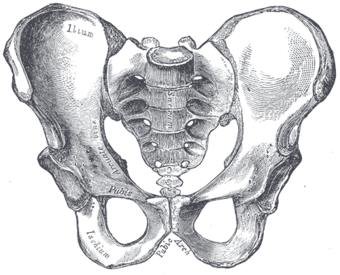

Pelvic girdle anatomy

Structure

The pelvic region of the trunk is the lower part of the trunk, between the abdomen and the thighs.[1] It includes several structures: the bony pelvis, the pelvic cavity, the pelvic floor, and the perineum. The bony pelvis (pelvic skeleton) is the part of the skeleton embedded in the pelvic region of the trunk. It is subdivided into the pelvic girdle and the pelvic spine. The pelvic girdle is composed of the appendicular hip bones (ilium, ischium, and pubis) oriented in a ring, and connects the pelvic region of the spine to the lower limbs. The pelvic spine consists of the sacrum and coccyx.[1]